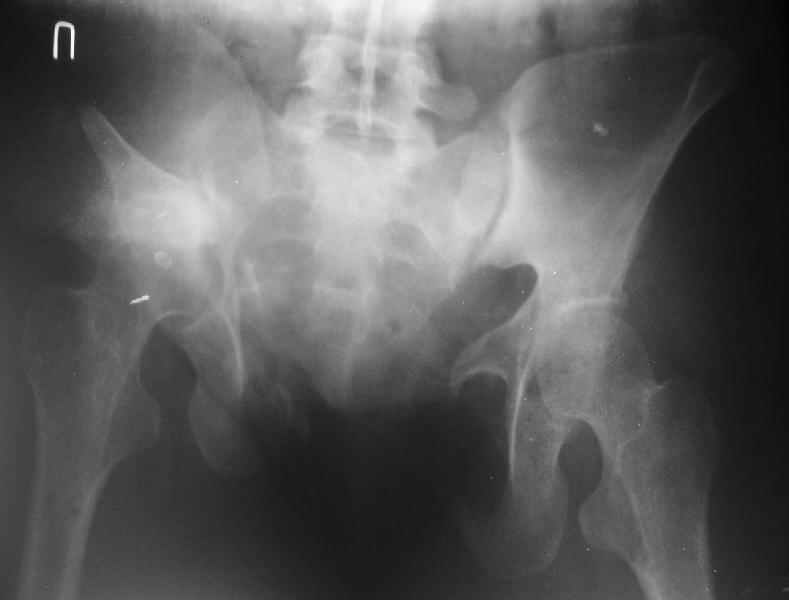

Дополнительно сообщаю, что больную беспокоят боли в области левого крестцово-подвздошного сочленения, в области правого болей нет. Кроме того, беспокоит укорочение конечности (ходит с компенсацией) без дополнительной опоры (в помещении), нарушение осанки (сколиоз, избыточный поясничный лордоз), боли в пояснице, невозможность стоять более 20-30 минут, спать без резинового круга под крестцом и подушкой под коленями, неудобство при сидении. Majeed 41 балл.

По просьбам коллег отправляем снимки таза: прямая, inlet, outlet, 2 дополнительные компьютерные томограммы.